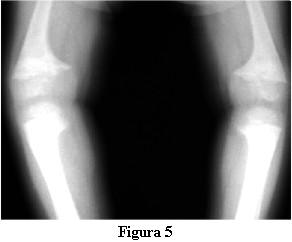

Las radiografías óseas mostraron una descalcificación global, los huesos largos incurvados y ensanchamiento de las metáfisis de los mismos en forma de copa (figuras 2 y 3).

En la evolución a los 3 meses de iniciado el tratamiento con calcitriol, a los 2 años y 9 meses, la marcha tiene las dificultades derivadas de las deformaciones de los miembros pero no presenta caídas, ni fatigabilidad, ni sudoración. La talla es de 81 cm , por debajo del percentil 3. La velocidad del crecimiento de los últimos 3 meses es de 8 cm/año. La fontanela anterior está completamente cerrada.Las radiografías óseas (figuras 4 y 5) muestran, a pesar del corto tiempo de evolución, una disminución del signo de la copa, con un progreso de la diáfisis hacia el tejido osteoide.